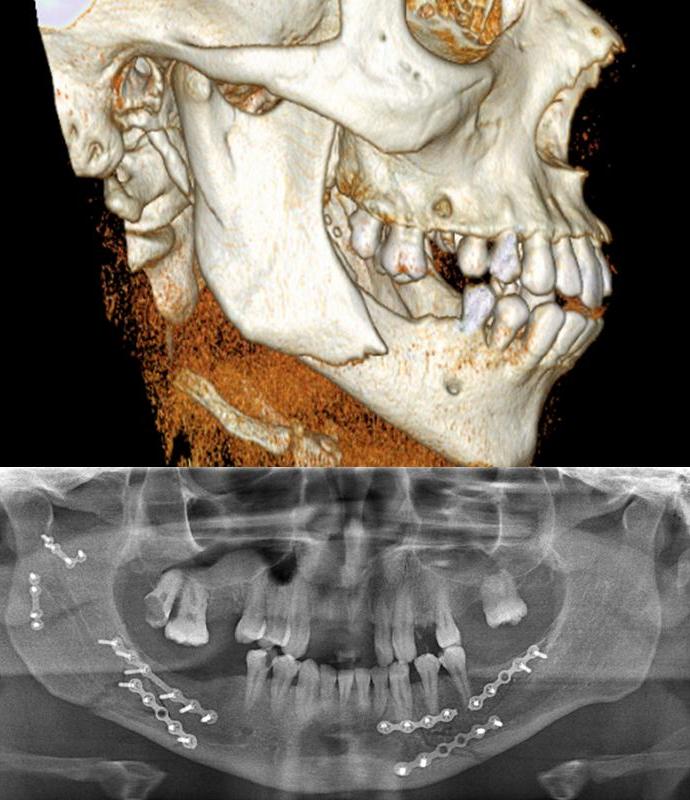

Diagnosis and treatment of soft (See Images Below) and hard tissue trauma of the oral and maxillofacial region (mandible fractures, zygoma/maxilla fractures, nasal/ethmoid fractures, mid-face (LeFort) fractures, skull fractures, frontal sinus fractures and orbital fractures)